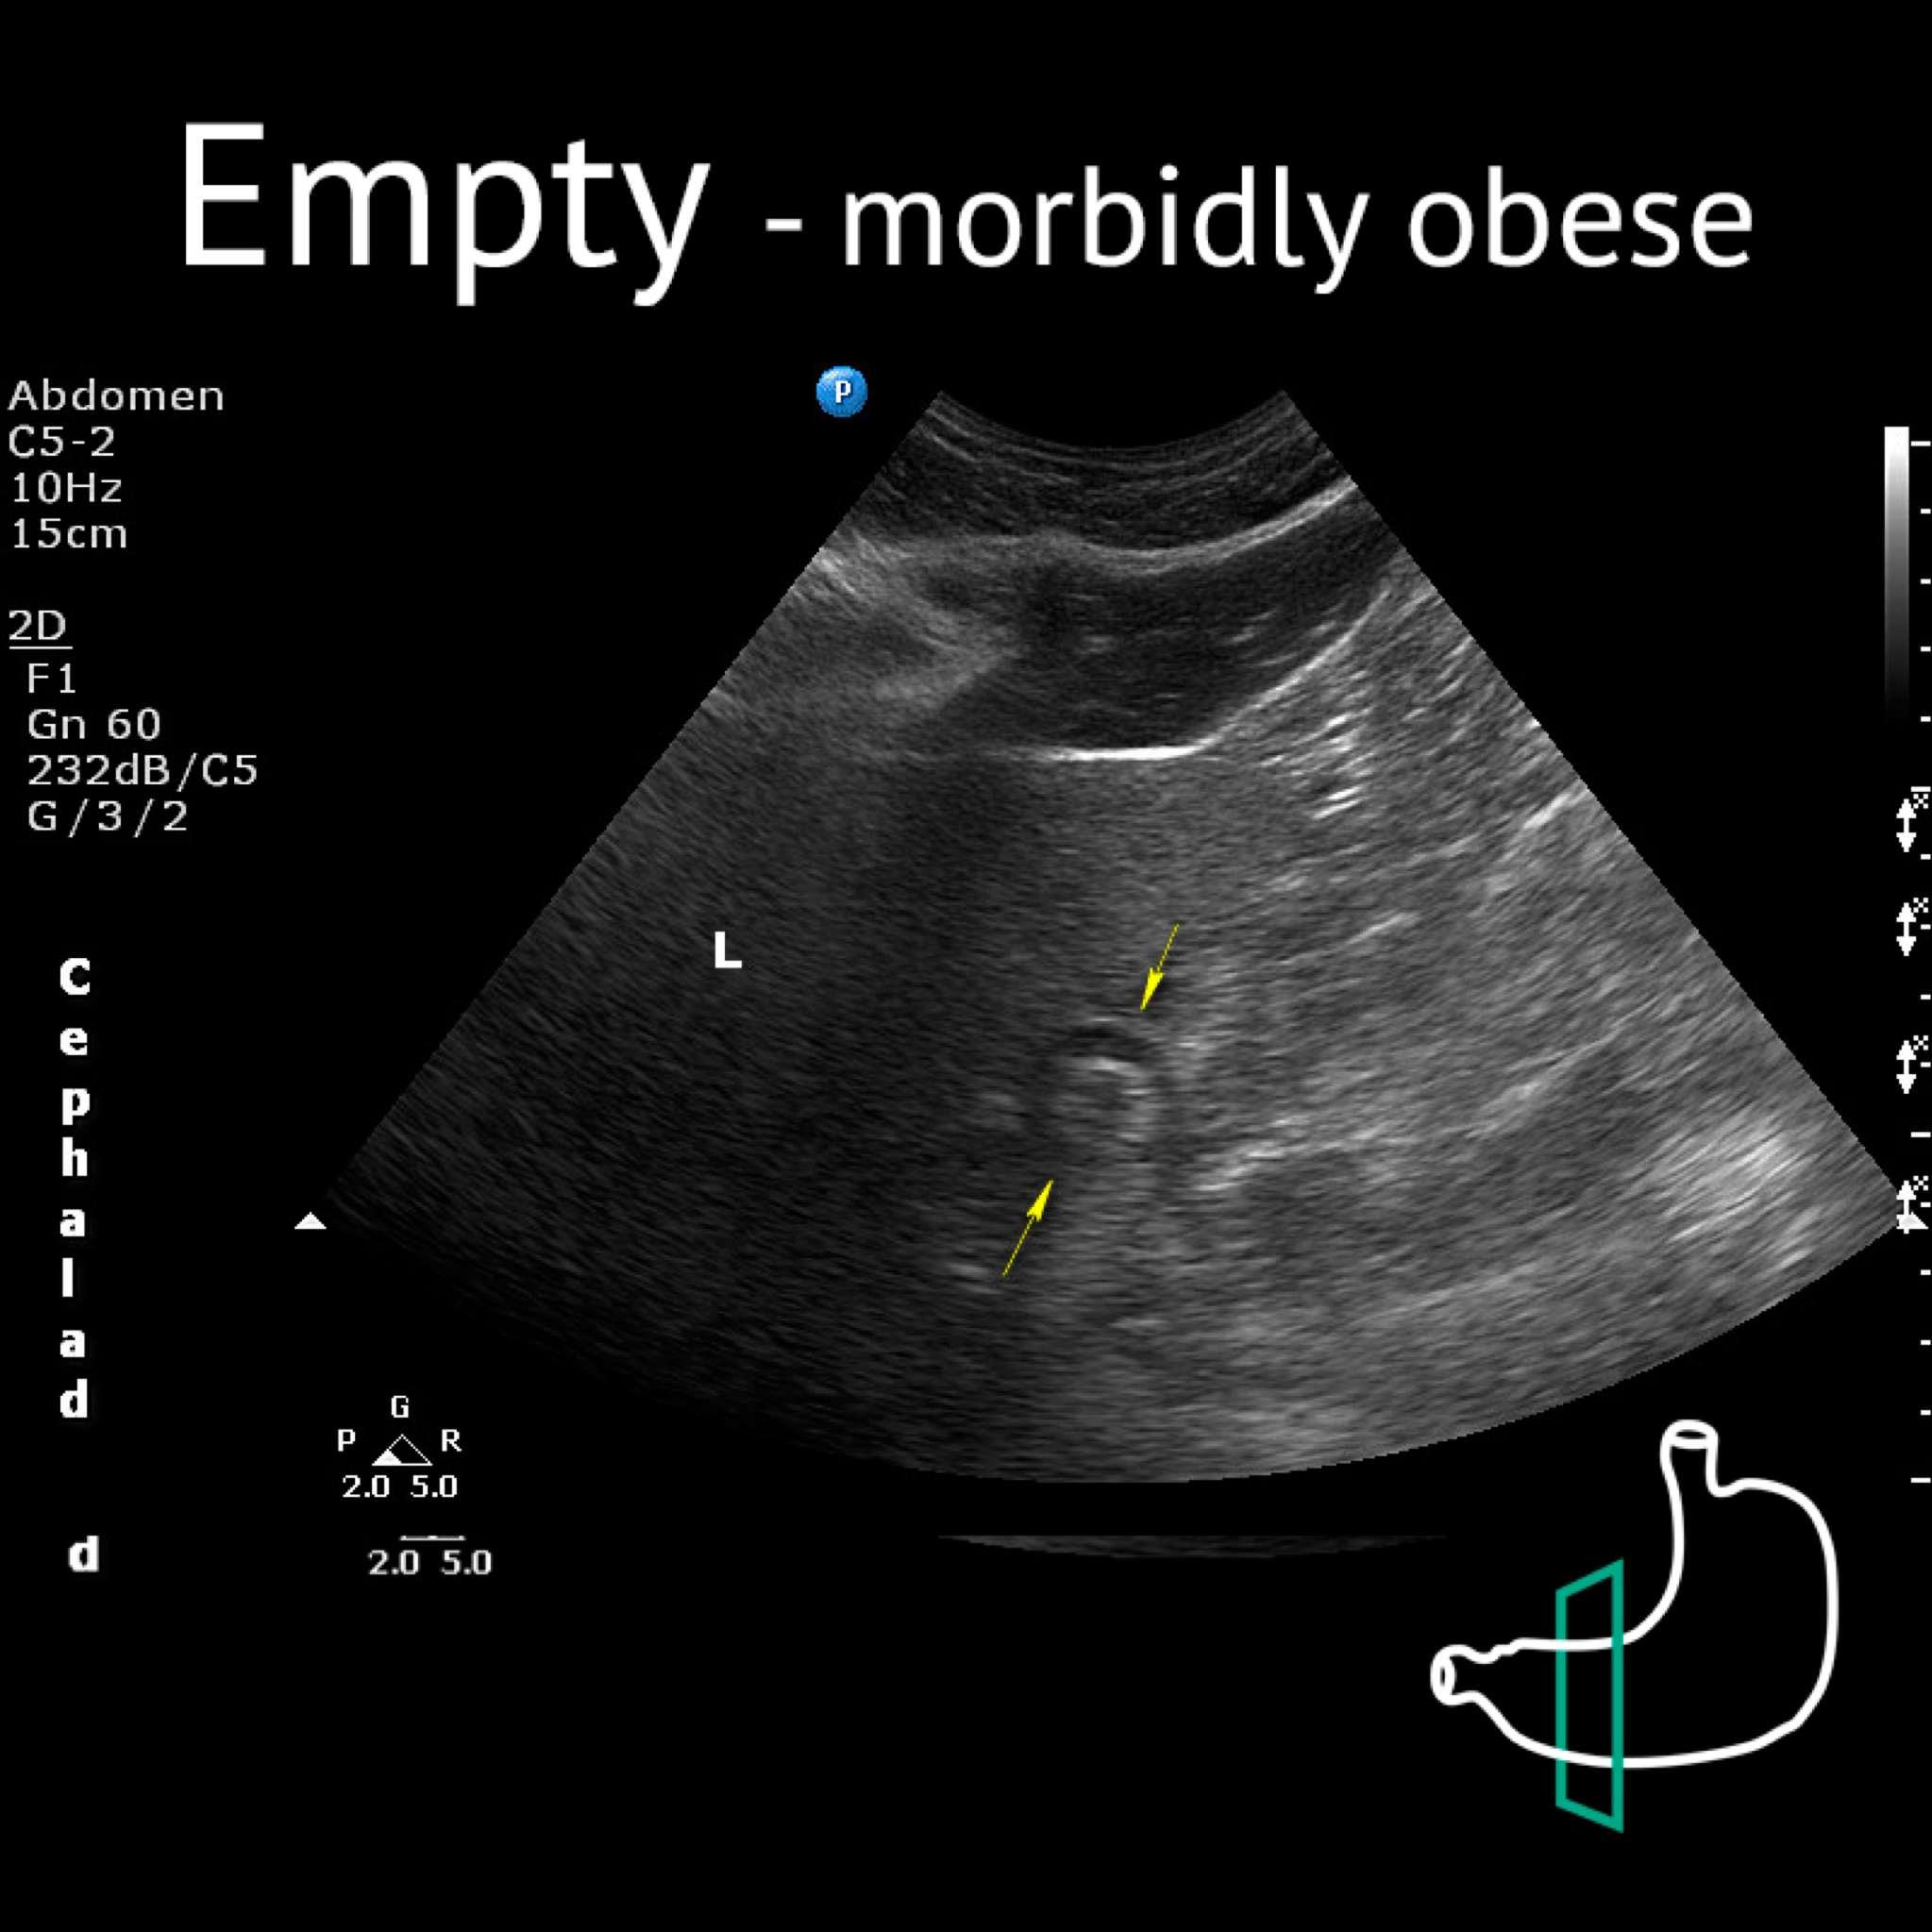

Ao: aorta; L: liver; P: pancreas; Sma: superior mesenteric artery; Yellow arrows: antrum